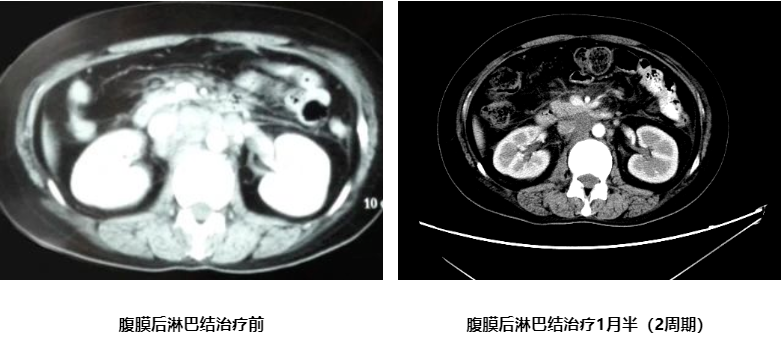

治疗2周期、4周期后肿瘤标志物及CT变化情况如下:

腹膜后淋巴结治疗3月(4周期)

日本有研究显示,对于合并腹主动脉旁淋巴结转移的胃癌患者,予以2周期顺铂联合S-1的术前化疗后施行D2+PAND(腹主动脉旁淋巴结切除)并以S-1单药维持至术后1年的治疗方案可以显著改善这类患者的总体生存及无病生存。但值得关注的是,对于经一线化疗后,腹主动脉旁肿大淋巴结已达到临床CR的情况下,是否仍然需要进行腹主动脉旁淋巴结切除的问题还存在争议,目前相关的临床研究正在进行中。在这个病例的治疗中,予以4周期的XELOX+赫赛汀的方案化疗后复查CT见腹主动脉旁淋巴结已完全消失,后进行手术切除,并行D2淋巴结清扫的治疗策略也是比较合理的。这里需要讨论的另外一个问题就是转化治疗的时长及手术时机的关系。由于目前严重缺乏这方面的大样本临床研究证据,因此,一般专家认为应效仿肠癌或间质瘤的转化治疗经验,争取在获得最佳药物治疗疗效的时候进行手术干预,因此,目前转化治疗的时长多不超过6周期。